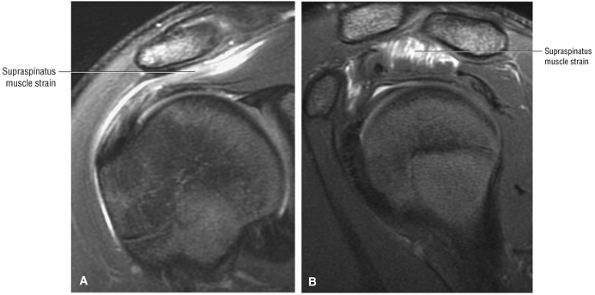

tendon tears and may result from fluid entering the muscle via a one-way valve mechanism through a partial-thickness tendon tear.